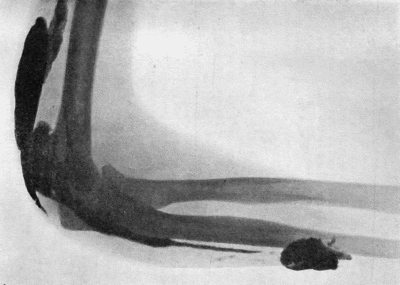

Fig. 1.—Ulcer of back of Hand covered by flap of skin raised from anterior abdominal wall. The lateral edges of the flap are divided after the graft has adhered.

| 1. | Ulcer of Back of Hand grafted from Abdominal Wall | 15 |

Another modification is to raise the flap but leave it connected at both ends like the piers of a bridge; this method is well suited to defects of skin on the dorsum of the fingers, hand and forearm, the bridge of skin is raised from the abdominal wall and the hand is passed beneath it and securely fixed in position; after an interval of 14 to 21 days, when the flap is assured of its blood supply, the piers of the bridge are divided (Fig. 1). With undermining it is usually easy to bring the edges of the gap in the abdominal wall together, even in children; the skin flap on the dorsum of the hand appears rather thick and prominent—almost like the pad of a boxing-glove—for some time, but the restoration of function in the capacity to flex the fingers is gratifying in the extreme.

Fig. 1.—Ulcer of back of Hand covered by flap of skin raised from anterior abdominal wall. The lateral edges of the flap are divided after the graft has adhered.